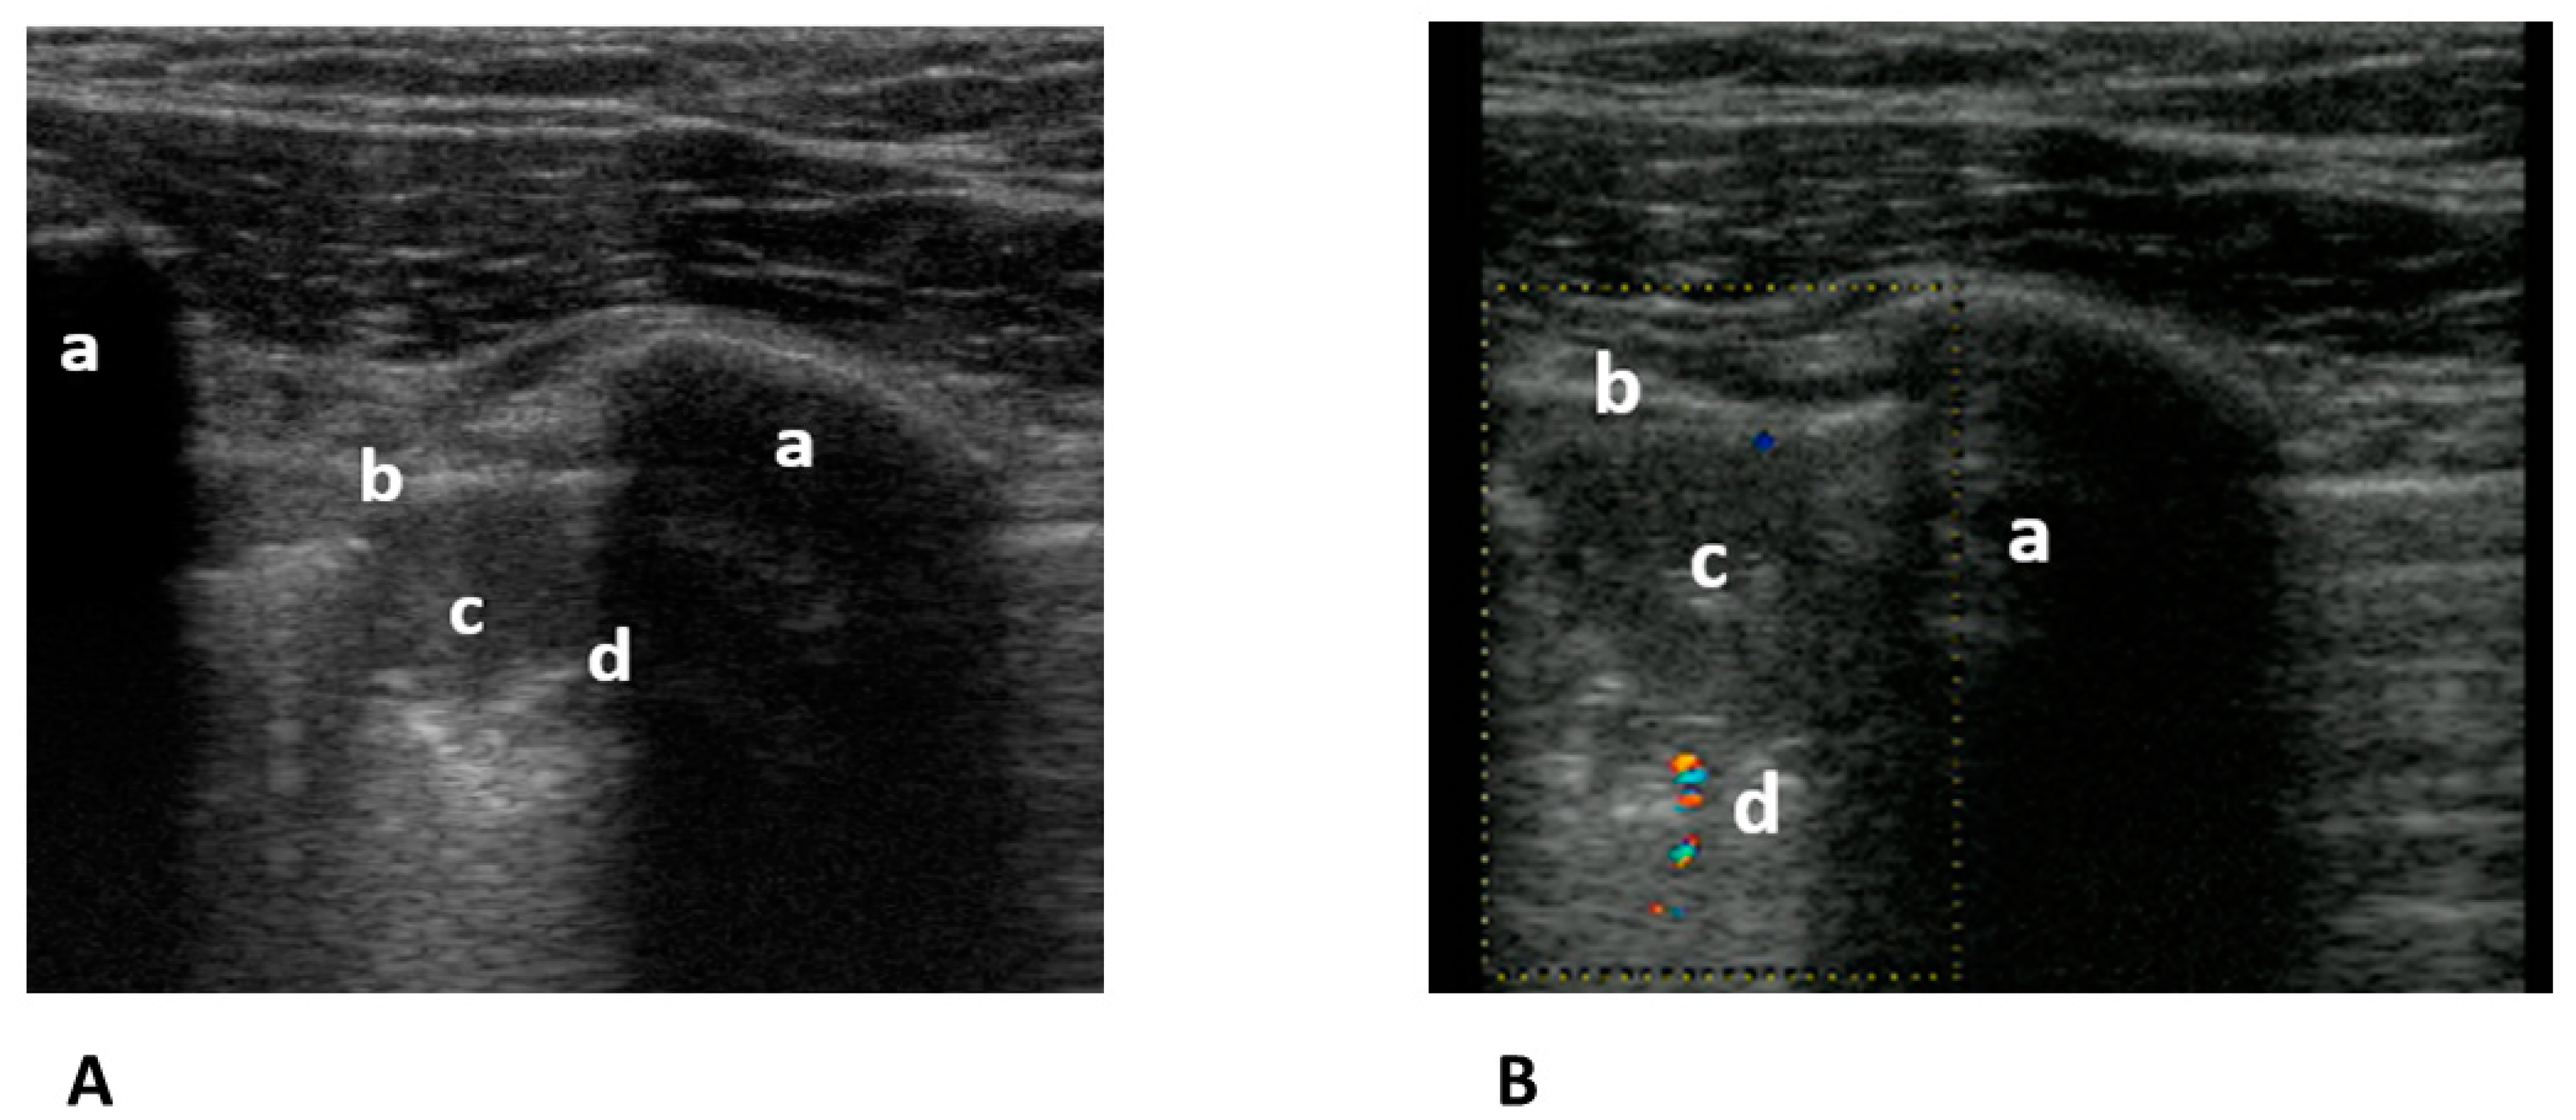

The gold standard for the diagnosis of pulmonary embolism is computed tomography pulmonary angiogram (CTPA). For many years, we have known that lung ultrasound (LUS) can diagnose pulmonary emboli that cause peripheral lung changes. To do so, at least two triangular (Figure 6A,B) or round hypoechogenic subpleural consolidations lacking central perfusion and usually measuring 1–2 cm in size must be detected [70].

Figure 6.

(A) Transthoracic longitudinal view: ribs (a), pleural line (b), and subpleural triangular consolidation (c) with central bronchus reflex (d). (B) Transthoracic longitudinal view: rib (a) pleural line (b), and second subpleural triangular consolidation (c) with obstructed vessel (d). Image courtesy of J. Osterwalder.

The pooled sensitivity of 82% (95% CI 72–88) and specificity of 95% (95% CI 79–95) of LUS for pulmonary embolism in a systematic review and meta-analysis are lower than those of CTPA. The sensitivities vary between 42 and 98% [71]. This wide range is probably the result of different diagnostic criteria for PE, patient selection, and the experience of the examiners. Nevertheless, together with compression ultrasonography of the leg veins and right heart echocardiography (triple sonography), the sensitivity could be increased to 90%, albeit at the cost of a decrease in specificity to 86% [72]. An inhomogeneous meta-analysis on this topic resulted in a sensitivity of 91% and specificity of 81% [73]. However, the reference variable was CTPA in only two studies and clinically derived criteria in five studies. In this context, one paper is interesting. The authors suggested that triple sonography saved 56% of CTPAs because of alternative diagnoses [74]. Despite these encouraging results and the great advantages over CTPAs without radiation exposure, contraindications, the risk of anaphylaxis, high costs, and long waiting times, this type of lung sonography is only offered routinely in a few emergency departments around the world. We believe that it is time to use ultrasound as a diagnostic rule-in tool for PE and thus save some patients and crowded emergency departments from many CTs.